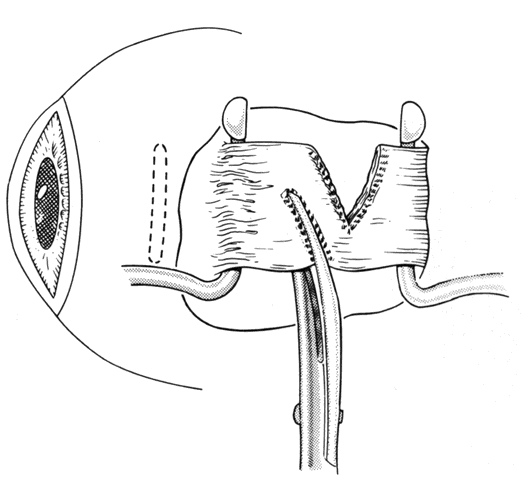

In some situations, a portion of a horizontal rectus may be left at the insertion site (Figs. 9 and 10). The muscle is usually split at the time of the initial procedure, and this can cause a shift of the distribution of force at the insertion and cause vertical misalignment. The pattern of the strabismus and the details of the previous surgery should provide clues to the problem and allow a logical approach for correcting the vertical deviation. Suspicions should be confirmed by careful dissection and exploration of the region of the muscle insertion. The importance of careful evaluation and elimination of mechanical restrictions cannot be overemphasized.4,10

Fig. 9. Residual exotropia or hypertropia can occur if a portion of the lateral rectus muscle is not recessed with the first procedure. To prevent this, care must be taken to incorporate all portions of the tendon when recessing an extraocular muscle.

Fig. 10. The pole test, or sweeping a Stevens muscle hook anterior to the insertion, will ensure that the entire tendon is on the Jameson muscle hook.